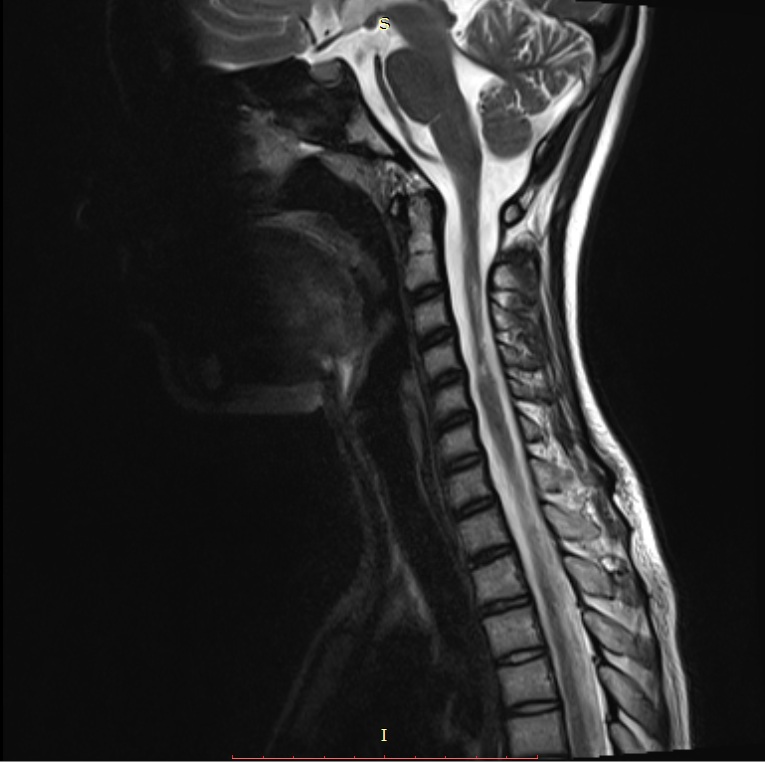

We validated our fast 3D volumetric image reconstruction method on 24 real life T2-MRI data (512×512512512512\times 512 pixels) of human spine with an inter slice gap of 333 to 5mm5𝑚𝑚5mm, and 30 real life T2-MRI data (512×512512512512\times 512 pixels) of human brain collected from Bangur Institute of Neurosciences, S.S.K.M, Kolkata and brain MRI data set of python.

Initially, the 2D2𝐷2D slices are split in 4 sub parts as shown in Figure 2 for a human spine, and the data set in divided in two parts. We use single instruction multiple data architecture using 8 logical cores. In parallel, for each block of sub-image, a 3D3𝐷3D matrix is created which is filled with the corresponding data leaving the specified slice gap in between slices as specified for each set as shown in Figure 3. Then edge preserved kriging interpolation is used to generate the 3d subimages. If we want to visualize these sub-images, then we can apply marching cube with color map and visualize the images as shown in Figure 4 and the complete 3D image for visualisation of full spine is as in Figure 5.

Refer to caption

(a) Captured slice #63 along the saggital plane for Slice sequence of Figure 7a

(b) 3D Reconstructed slice #63 along the saggital plane for slice sequence of Figure 7b

Figure 8: Slice #63 for a human spine along the saggital plane for slice sequence of Figure 7b while capture vs after reconstruction

(a) Input Sequence of slices with slice gap of 3mm

(b) Reconstructed 3D image

Figure 9: 3D reconstruction from MRI image sequence of a human full spine

(a) Captured slice #148 along the axial plane for slice sequence of Figure 9a

(b) Reconstructed slice #148 along the axial plane for slice sequence of Figure 9b

Figure 10: Slice #148 for a human spine along the axial plane for slice sequence of Figure 9b while capture vs after reconstruction

(a) Input Sequence of slices with slice gap of 5mm

(b) Reconstructed 3D

Figure 11: 3D reconstruction from MRI image sequence of human lumbar spine

In Figure 7 an example of 3D volumetric reconstruction, visualization as well as slicing are depicted. Figures 9, 11, 12 provide the results of our 3D reconstruction from a sequence of 2D slices for a full spine, a lumbar spine and a brain respectively. We compared the results after slicing with the available ground truth data (Figures 6, 8, 10, 13 for human lumbar along coronal, saggital, axial planes and human brain along sagittal plane respectively) based on mutual information, entropy, root mean square error and structural similarity index (see Appendix D). The average time taken by our 3D3𝐷3D reconstruction fo human spine is 54 seconds, depending on the size of the input data set. The time taken for slicing is a fraction of a second. The average accuracy percentage of our method, as shown in Table 2, is calculated as :